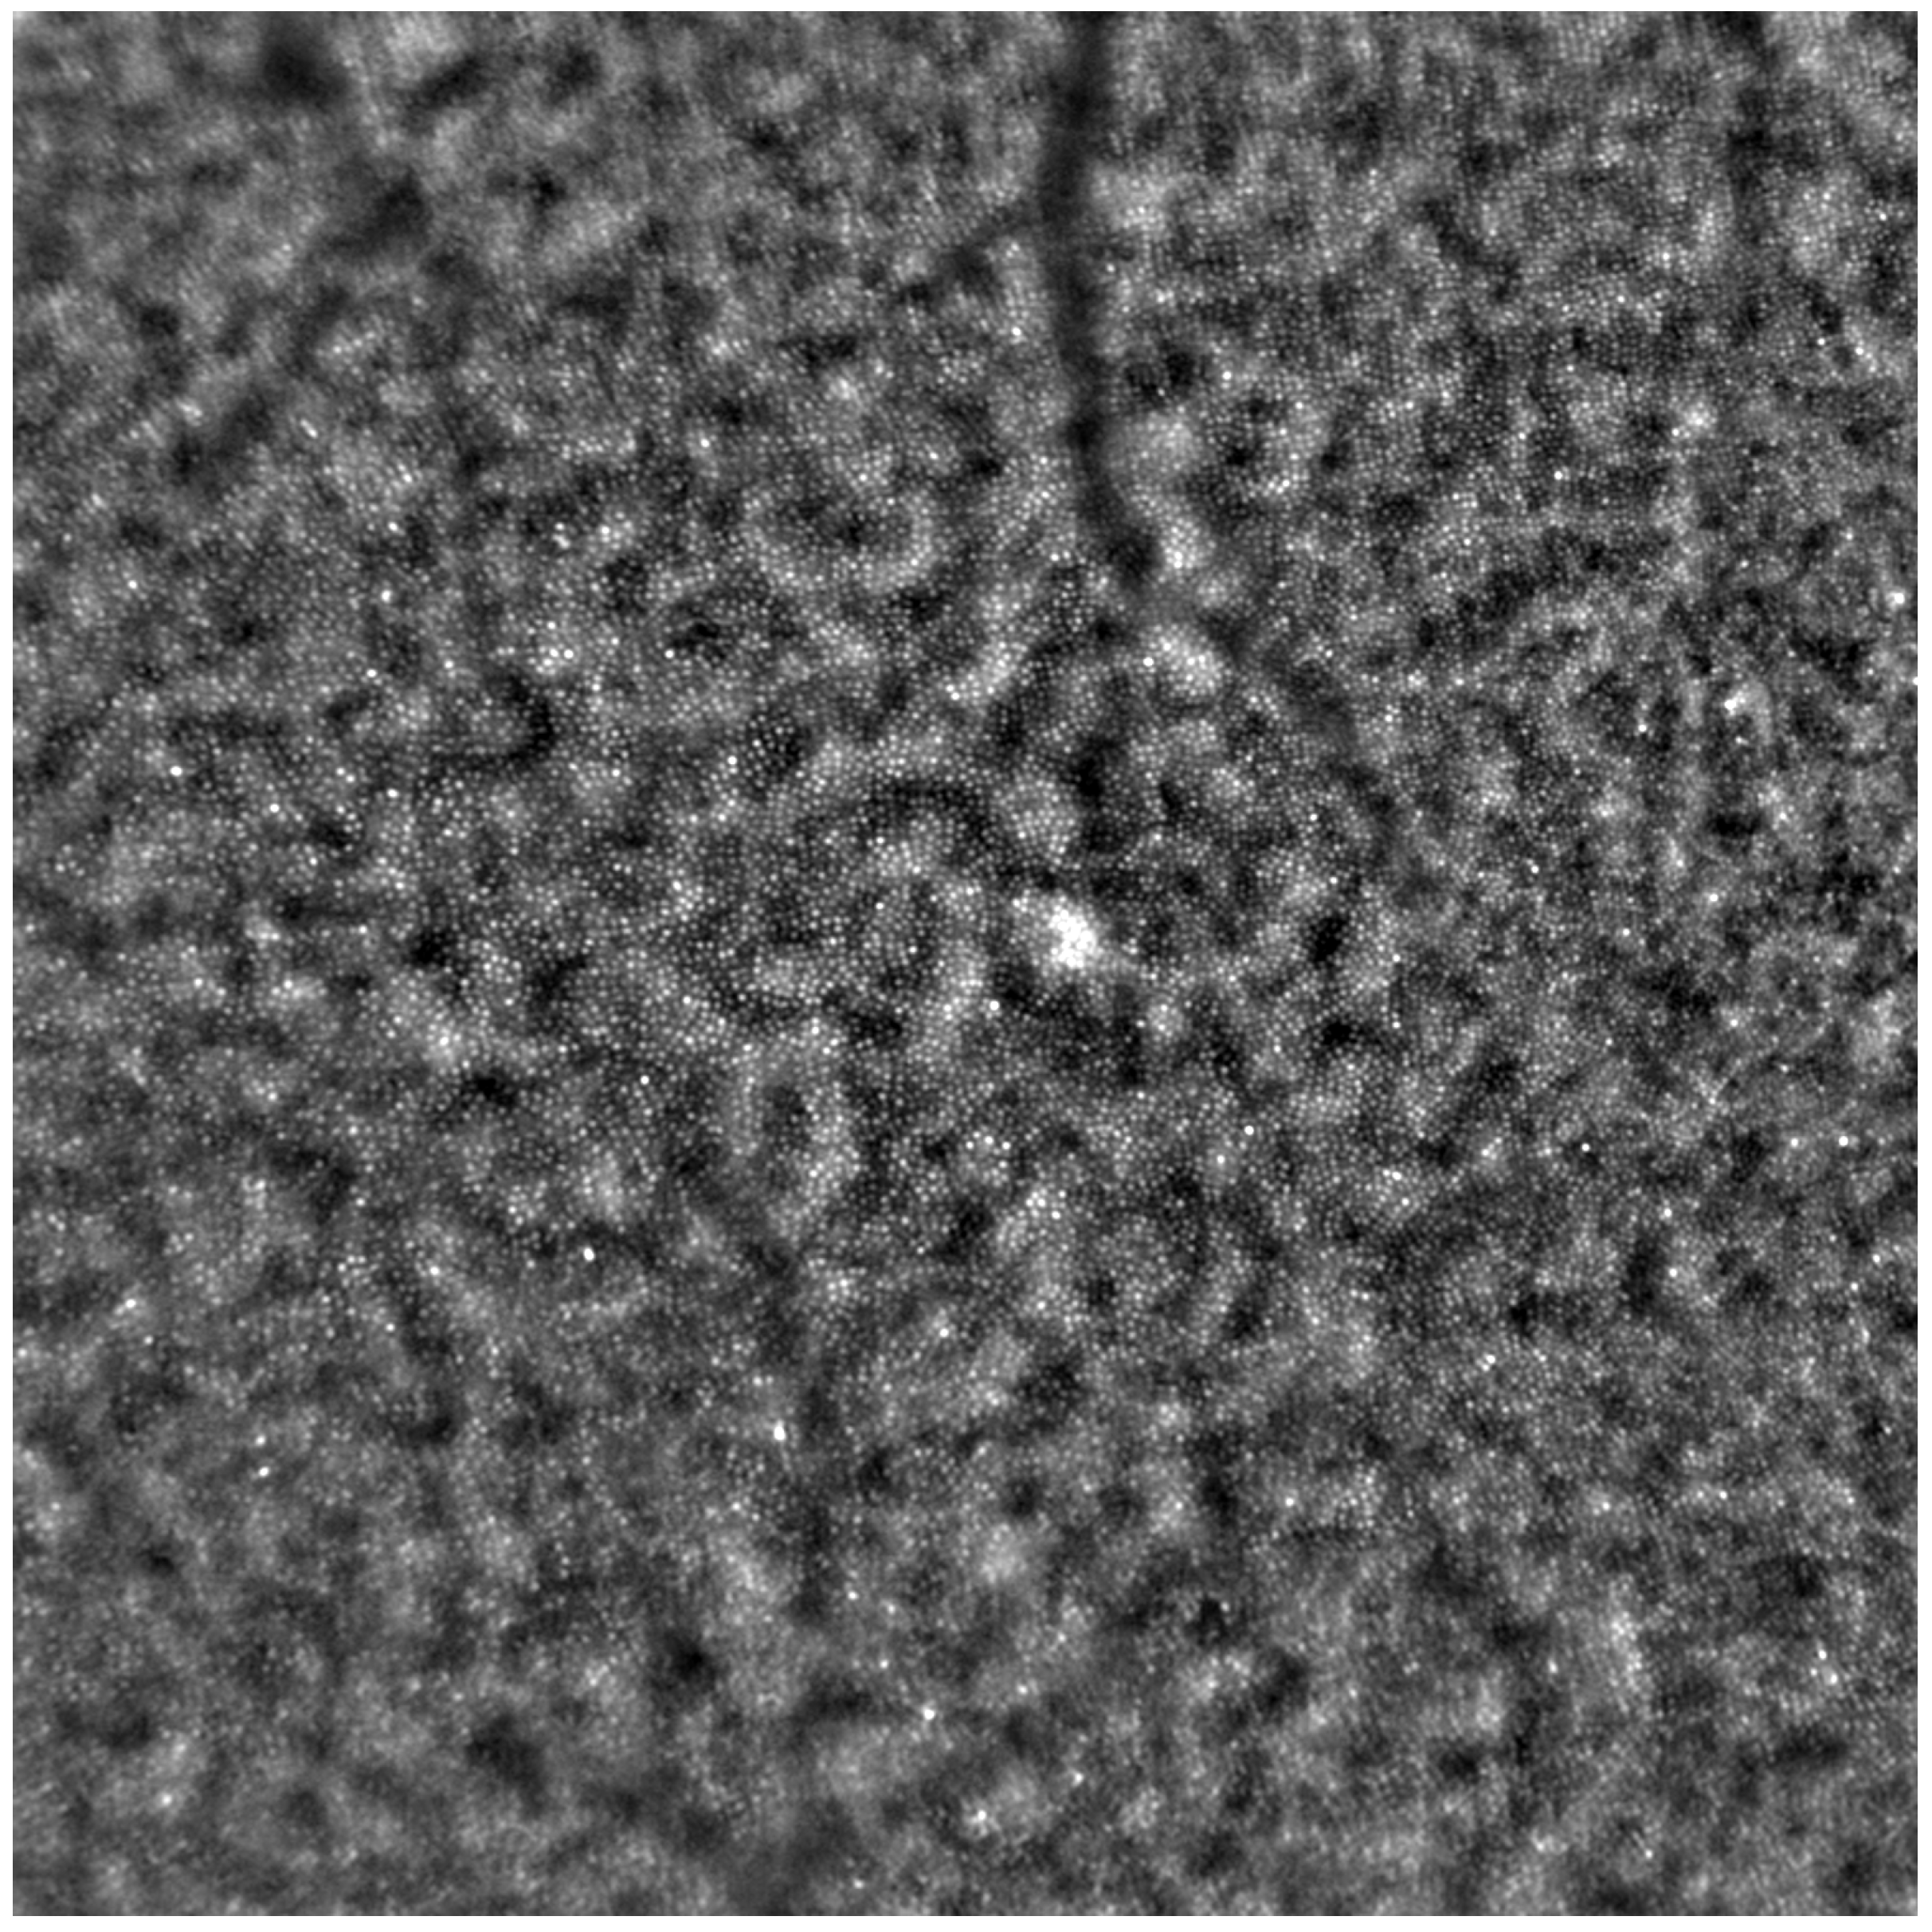

Adaptive optics retinal images depicting a healthy eye, CD, CRD, and STGD are presented in Figure 1, Figure 2, Figure 3 and Figure 4.

Figure 1 depicts the photoreceptor mosaic in a healthy eye. The image is taken paracentrally (2 ° superiorly) due to the limited ability of foveal image acquisition by Rtx™ [17]. By changing the focus point, the quality of an acquired image provides the assessment of photoreceptor parameters in parafoveal cones. The aberration and noise found in Figure 2, Figure 3 and Figure 4 are considered to be the result of poor fixation in eyes with impaired central vision in the course of macular disease. This issue has been addressed in our study. The assessment of factors predisposing for obtaining inadequate image quality was taken into consideration further in this article.

Cone mosaic disruption is an abnormality typical of IRDs. The cone and rod spacing is increased in IRDs compared to healthy retinas [18]. Additionally, poor image quality, likely resulting from inadequate fixation in eyes with low visual acuity, is a problem that, in some cases, makes image acquisition impossible [19,20]. In STGD, as well as in other IRDs, the “dark spaces” depicting areas of disrupted cone structure and abnormal cone reflectance have been described [21,22].

Figure 3. An adaptive optics image of photoreceptors in an eye affected by cone–rod dystrophy (Rtx1™, Imagine Eyes, France). Throughout the image, the cones are not clearly visible. Observe the “dark spaces” scattered within the cone mosaic across various regions of the picture.